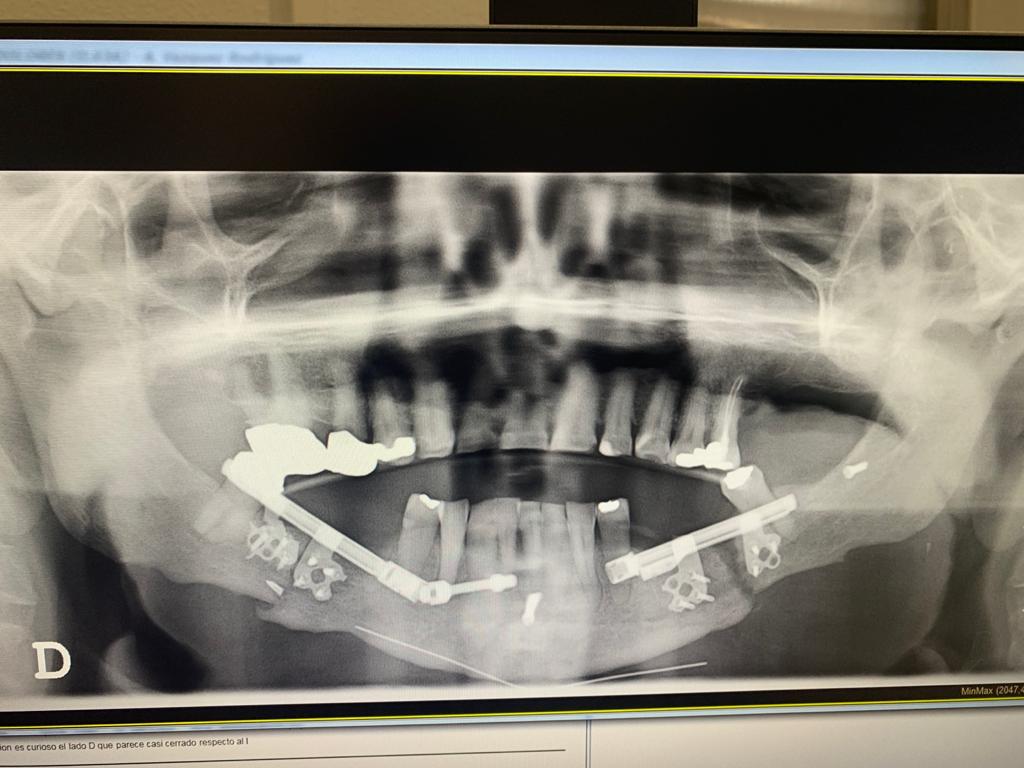

Description: Intervención de apnea severa Dr. Antonio Vázquez, cirujano maxilofacial especialista en la cura de la apnea La imagen corresponde a un paciente con apnea severa previamente intervenida de avance bimaxilar y distracción mandibular hasta conseguir 0 apneas.